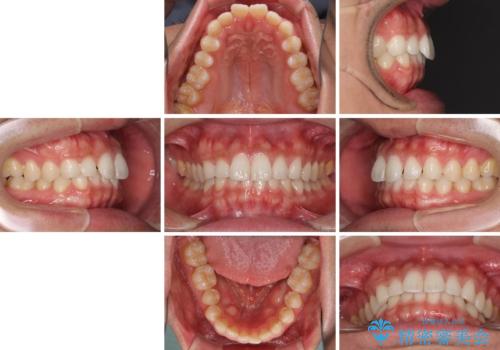

- 患者様

- 20代男性

- 矯正装置

- インビザライン

- 治療期間

- 1年5ヶ月

- 治療計画

- 上下の前歯の隙間を気にして来院された患者様です。

インビザラインを用い、上下歯列のスペースを閉じていくこととしました。